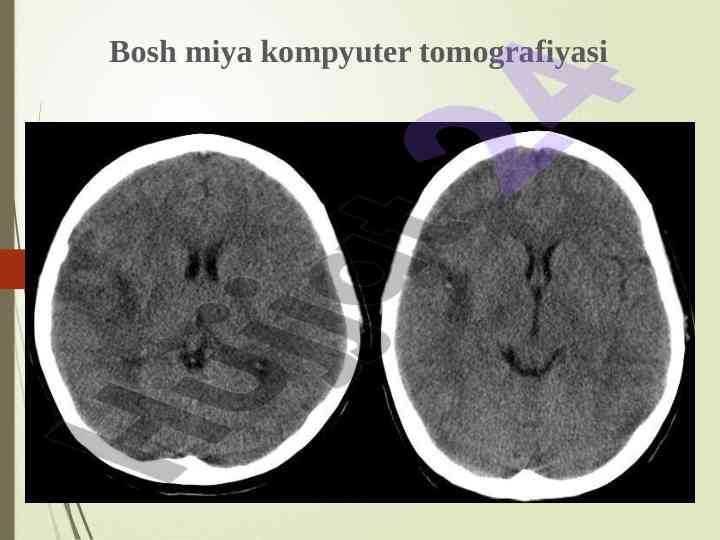

Asab kasalliklarini instrumental diagnostika uchun EEG, UZDG, ExoEG va boshqa usullar orqali nevrologik tashhisni aniqlash va kasallik tarixini tahlil qilish jarayonlari haqida ma'lumot.